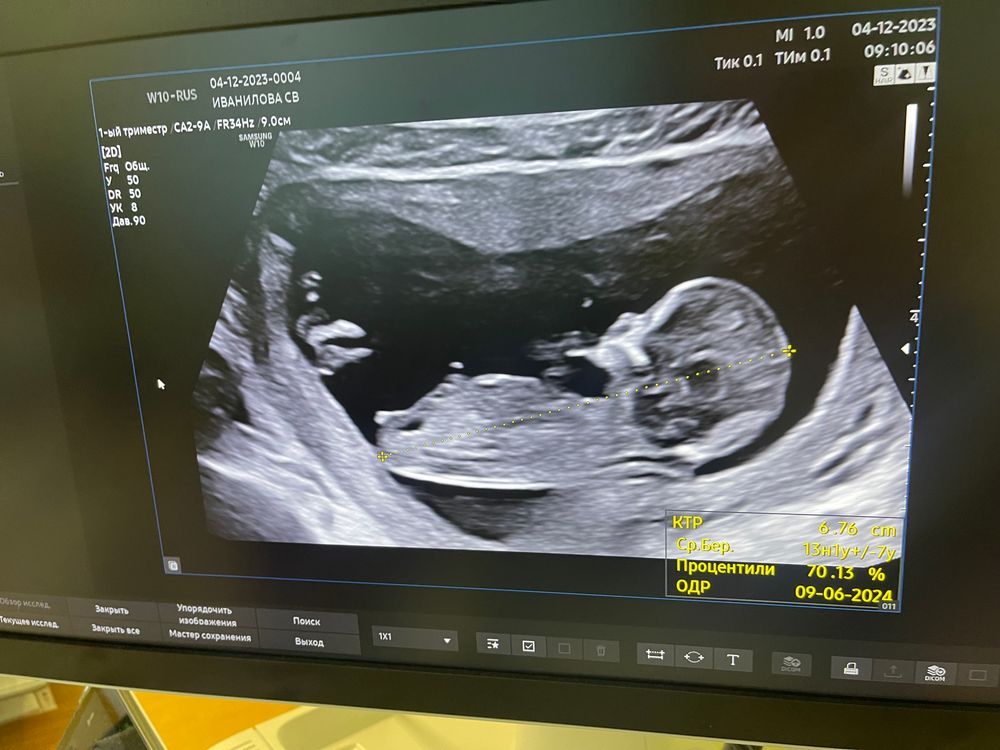

1 скрининг ✅